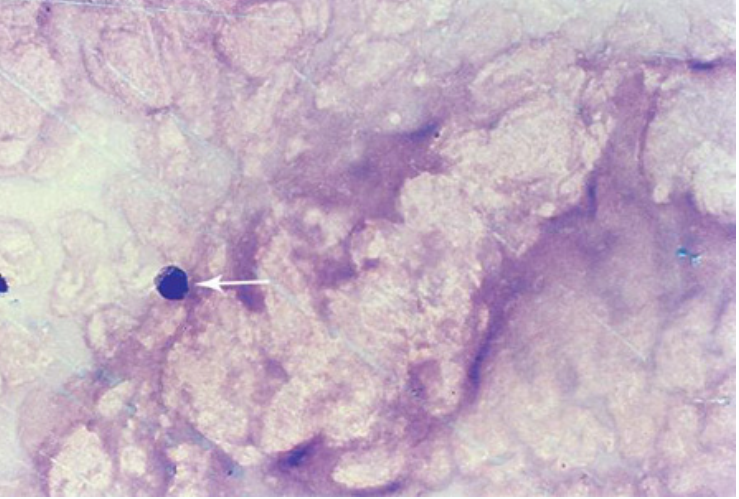

term image

DJD w osteoclast